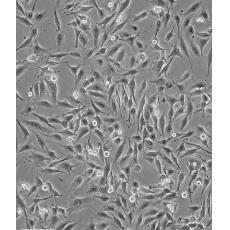

MDA-MB-435

中文名稱 人乳腺癌高轉移細胞

組織來源 乳腺癌

生長特性 loosely adherent with floating clusters

形態特征 epithelial

細胞描述 該細胞1976年建系,源自一位48歲患有乳腺癌女性的胸腔積液,但近來有研究證明該細胞被M14黑色素瘤細胞污染。